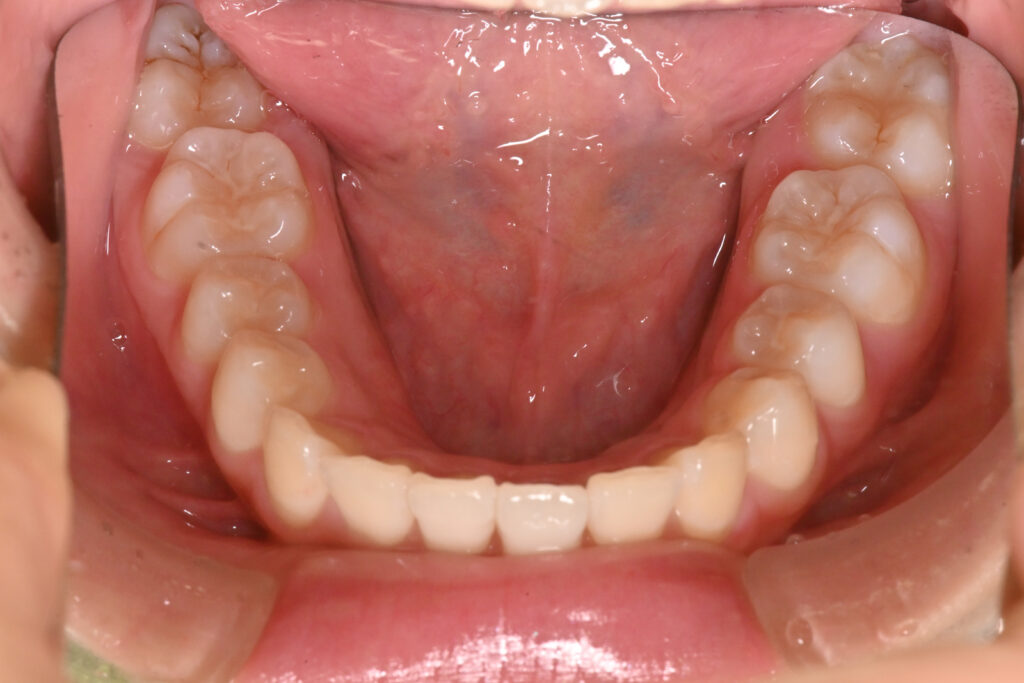

下顎

治療前

治療後